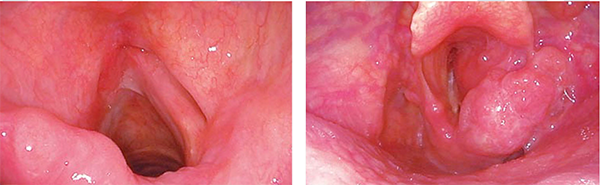

Although it has a small diameter, the scope still illuminates abroad area, providing a detailed image of any lesions withinthe field of view. This exceptional luminosity is especialyuseful when observing with NBl.

Wide field of view

The ENF-VH has a viewing angle of 110° And with HD resolution and exceptional illumination, every corner of the field can bethoroughly inspected.

During endoscopic observation, NBI enhances visualizationof the capillary network and mucosal morphology.

White Light NBI

Astounding Image Quality

With advances in CCD technology, ENF-VH delivers HD images, which show even greaterdetail for examinations.